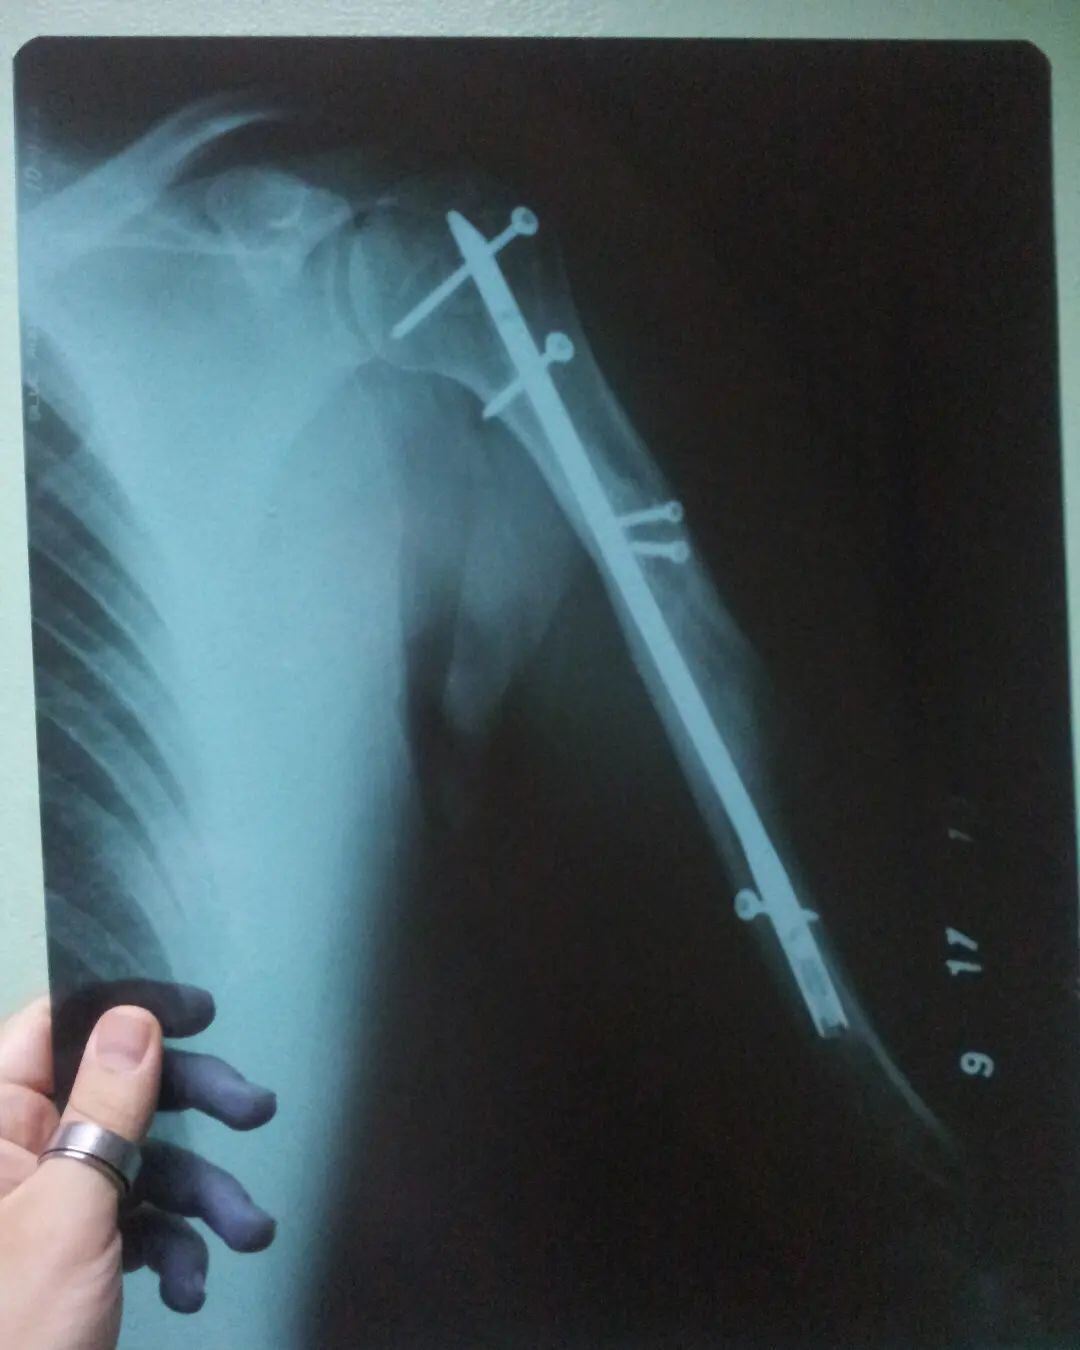

Según mostró el artista urbano, quedó como un Cristo, luego de ser atropellado por un carro, hace 13 años, que lo llevó a que lo operaran de su brazo derecho y le pusieran varios pines.

En las imágenes que mostró se ve su extremidad toda magullada, luego del bombazo que recibió.

Por suerte para él, fue solamente un mal recuerdo y ya mueve su brazo con normalidad ayudado por los pines.